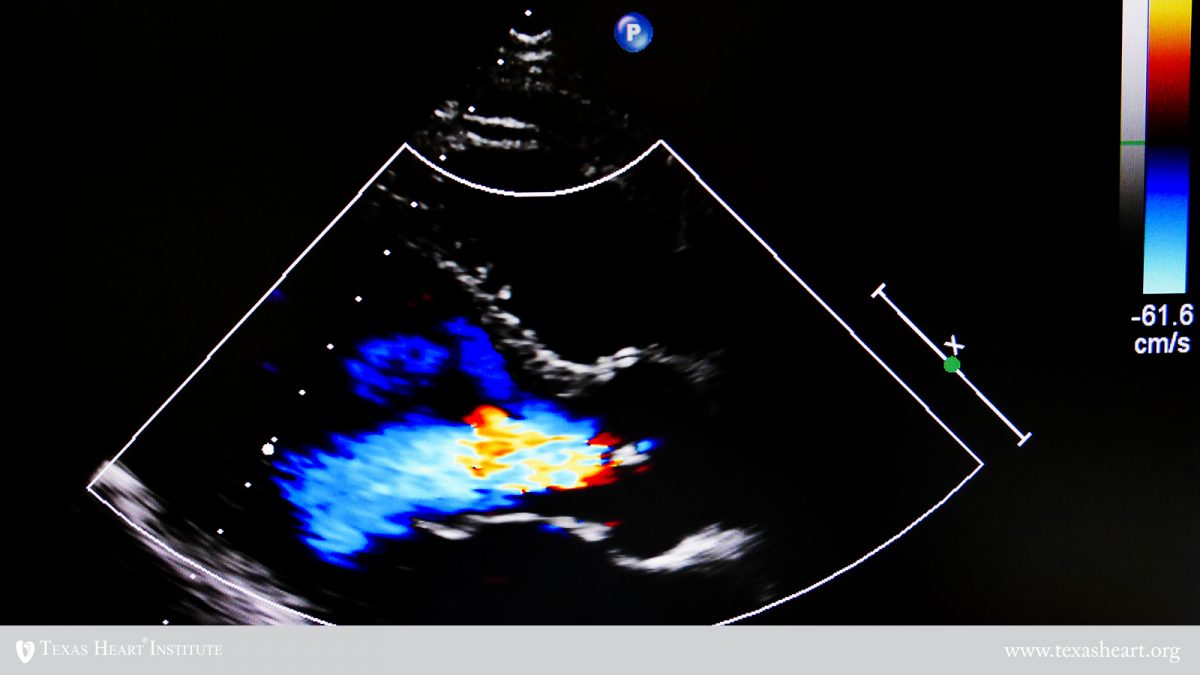

from www.texasheart.org

Mitral Valve Prolapse (MVP) Texas Heart Institute

Mitral Valve Prolapse (MVP) Texas Heart Institute Sharp Chest Pain Mitral Valve Prolapse The chest pain may be. This backflow of blood may result in a heart murmur. Mvp symptoms are the sensations or feelings that people with the condition may experience. Mitral valve prolapse is a type of heart valve disease that affects the valve between the left heart chambers. Chest pain is the most frequent symptom in people who have symptoms. Sharp Chest Pain Mitral Valve Prolapse.